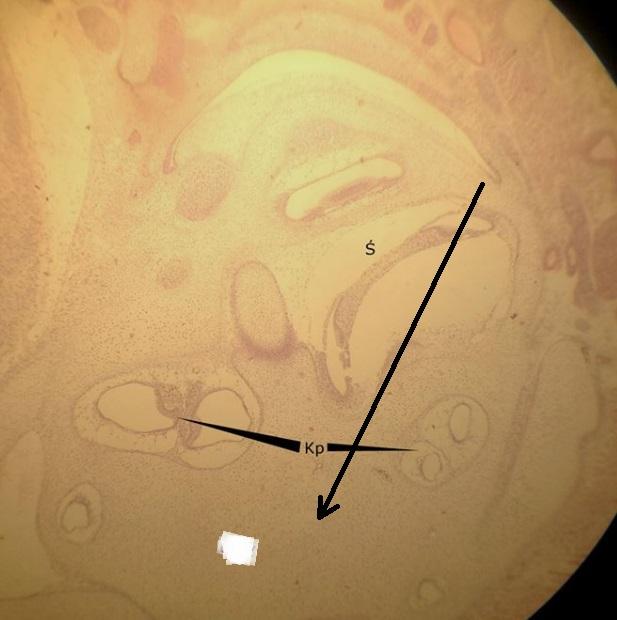

Pytanie 364

chrząstka szklista (preparat rozwojowy z głowy szczura, okolice ucha wewnętrznego)